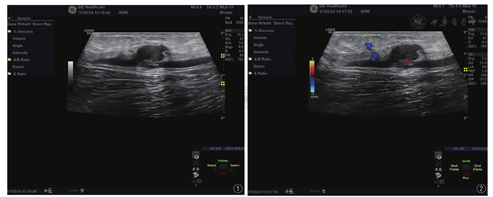

患者女性,61岁,半年前无意中发现左股内侧皮下包块,大小约1 cm×1 cm,无发热、疼痛等不适,初起未在意,未行诊治,其后患者自觉左股内侧皮下包块渐长大,且出现疼痛,遂来我院就诊,就诊时查体左股内侧皮肤无红肿,皮下深部组织层内可扪及大小约4 cm×3 cm质软包块,边界尚清晰,有触压痛。自发病以来,患者精神可,体力正常,食欲正常,睡眠可,体重无变化,大小便正常,无胸闷、心慌、气短,无咳嗽、咳痰或咯血、呕血等。彩超结果显示:超声所见:左大腿中段皮下脂肪层内探及低回声包块,边界尚清,形态欠规则,大小约17 cm×11 mm,后方紧邻大隐静脉,局部与大隐静脉分界不清,该处大隐静脉连续性差,管腔透声差。超声提示(图1,图2):左大腿中段皮下脂肪层低回声包块,性质待定,建议进一步检查。病理结果:左股部梭形细胞肿瘤,结合免疫组化染色结果,考虑上皮样肉瘤。免疫组化染色结果:CK(+)、S-100(个别细胞+)、CD68(-)、SMA(-)、CD34(+)、P53(7%+)、Ki-67(约25%+)、NSE(灶+)、Vimentin(+)、CK5/6(+)、CD31(血管+)、EMA(+)、Desmin(-)。

超声检查简便易行,安全无辐射,能清晰显示病变范围、结构、血运及对周围组织的浸润情况,在本病的诊断、治疗及随访中起了重要作用。